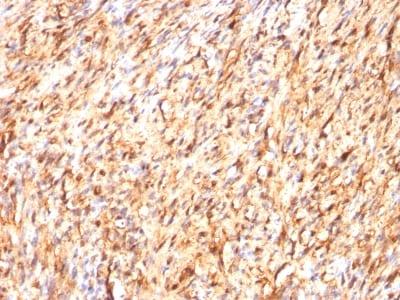

Positive Control

Brain, Melanoma

Melanoma

S100 belongs to the family of calcium binding proteins. S100A and S100B proteins are two members of the S100 family. S100A is composed of an alpha and a beta chain whereas S100B is composed of two beta chains. This antibody is specific against an epitope located on the beta-chain (i.e. in S-100A and S-100B) but not on the alpha-chain of S-100 (i.e. in S-100A and S100A0). This antibody can be used to localize S-100A and S-100B in various tissue sections. S-100 protein has been found in normal melanocytes, Langerhans cells, histiocytes, chondrocytes, lipocytes, skeletal and cardiac muscle, Schwann cells, epithelial and myoepithelial cells of the breast, salivary and sweat glands, as well as in glial cells. Neoplasms derived from these cells also express S-100 protein, albeit non-uniformly. A large number of well-differentiated tumors of the salivary gland, adipose and cartilaginous tissue, and Schwann cell-derived tumors express S-100 protein. Almost all malignant melanomas and cases of histiocytosis X are positive for S-100 protein.Primary antibodies are available purified, or with a selection of fluorescent CF® Dyes and other labels. CF® Dyes offer exceptional brightness and photostability. Note: Conjugates of blue fluorescent dyes like CF®405S and CF®405M are not recommended for detecting low abundance targets, because blue dyes have lower fluorescence and can give higher non-specific background than other dye colors.

Higher concentration may be required for direct detection using primary antibody conjugates than for indirect detection with secondary antibody|Immunofluorescence: 1-2 ug/mL|Immunohistology formalin-fixed 0.25-0.5 ug/mL|Staining of formalin-fixed tissues requires boiling tissue sections in 10 mM citrate buffer, pH 6.0, for 10-20 min followed by cooling at RT for 20 minutes|Flow Cytometry 0.5-1 ug/million cells/0.1 mL|Western blotting 0.5-1 ug/mL|Optimal dilution for a specific application should be determined by user